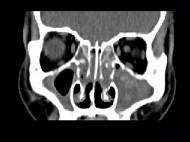

男,14岁,持续性鼻塞、嗅觉减退,流脓涕数年,CT检查如图,最可能的诊断为 ( )

• A.鼻炎及鼻窦炎

• D.鼻及鼻窦息肉

答案: A